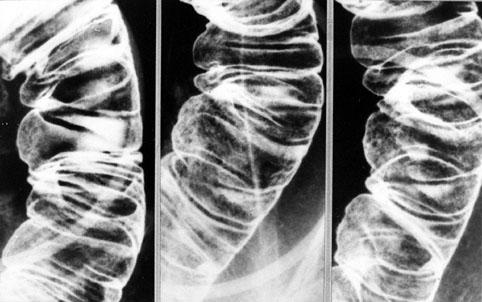

미만성으로 조악한 점막면을 보인 장 아밀로이드증

염증성・궤양성 질환/소화관 유전분증

소장/기타

X-P